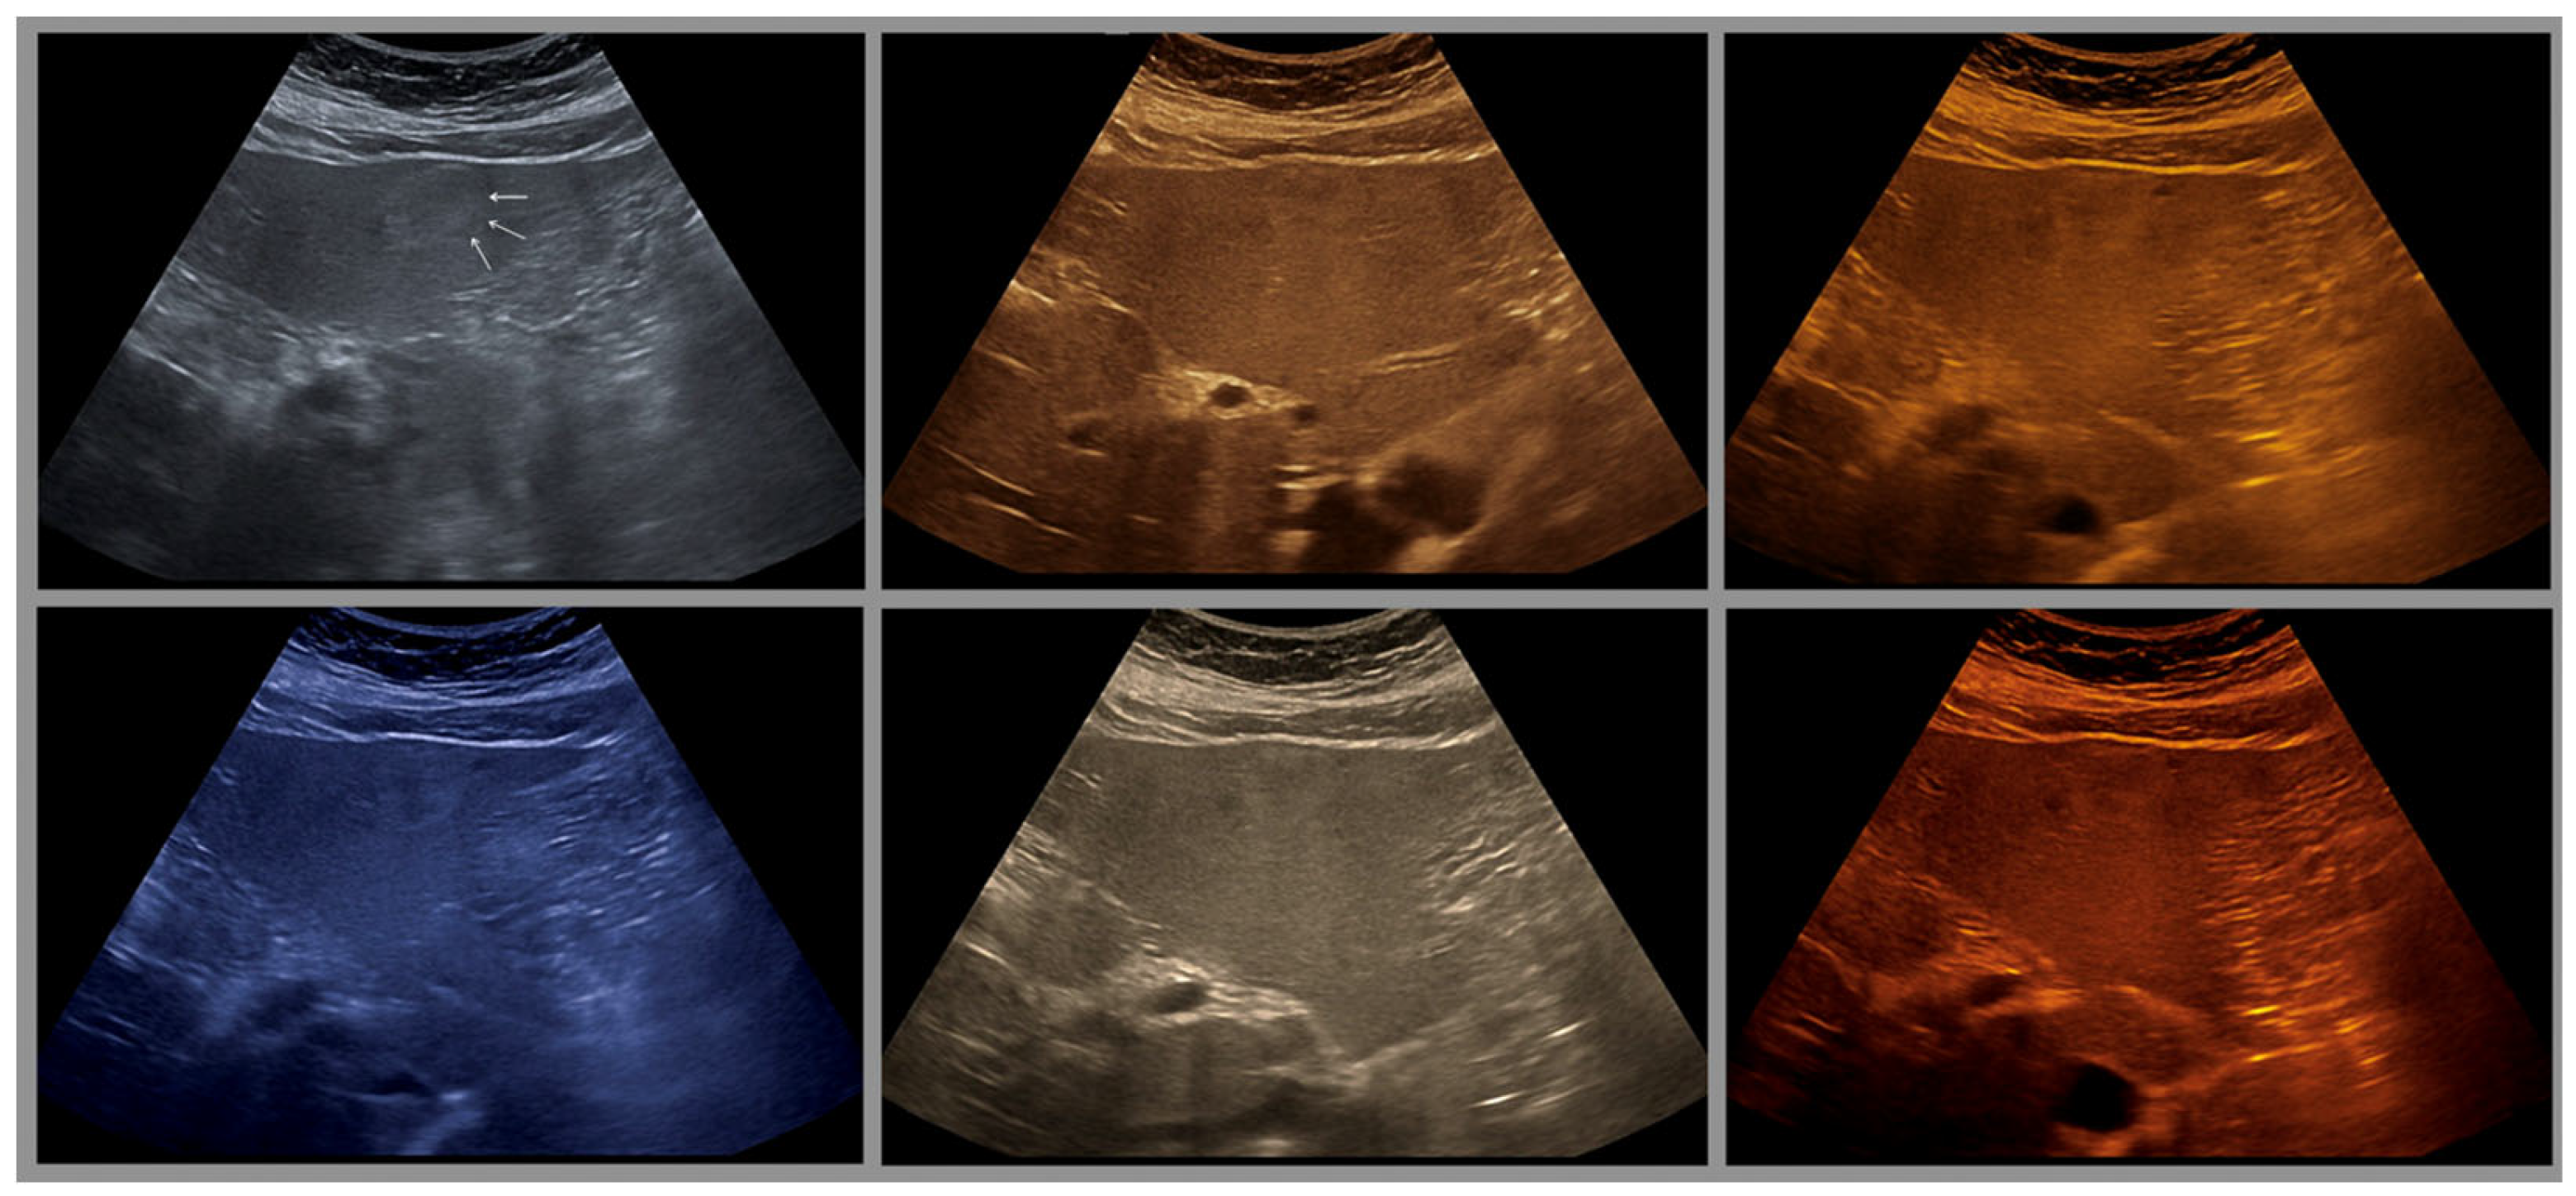

Is There an Ideal Color Map?

- The combination with speckle filters available in all high-end devices, similar to the low-pass filters used by Bleck et al. (1994) for tissue visualization [5], also yields significantly improved visualization results (Figure 5, Figure 6 and Figure 7). In principle, applications with new visualized texture analyses, such as random field models, are also conceivable [76,77].

- Merkel, D.; Brinkmann, E.; Kammer, J.C.; Kohler, M.; Wiens, D.; Derwahl, K.M. Comparison Between Various Color Spectra and Conventional Grayscale Imaging for Detection of Parenchymal Liver Lesions With B-Mode Sonography. J. Ultrasound Med. Off. J. Am. Inst. Ultrasound Med. 2015, 34, 1529–1534. [Google Scholar] [CrossRef]

| Color | Advantages |

|---|---|

| Sepia (Yellow-Brown) | Mimics familiar tones from black-and-white photography |

| Enhances contrast while preserving anatomical detail | |

| Offers intuitive brightness mapping (lighter tones = more echogenic areas) | |

| Preferred by students and experts alike | |

| Blue | Provides excellent depth perception |

| Reduces visual fatigue by avoiding glare and high saturation | |

| Often favored by experienced examiners for high-resolution detail | |

| Facilitates alertness and performance on tasks requiring sustained attention | |

| Green (muted tones) | Offers a balanced hue that avoids excessive saturation |

| Enhances intermediate echogenicity levels without causing artifacts | |

| Especially helpful for liver and parenchymal tissue imaging |